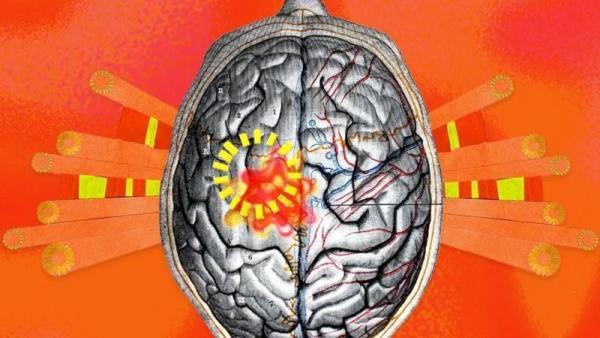

मायग्रेन म्हणजे प्रचंड डोकेदुखी, आणि हा एक अतिशय गुंतागुतींचा आजार आहे. जागतिक आरोग्य संघटनेनुसार जवळपास एक अब्ज लोक या आजाराने त्रस्त आहेत.

हा एक असा आजार आहे ज्यामुळे डोकेदुखी इतकी तीव्र होते की रोजचं काम करणंसुद्धा कठीण होतं.

मायग्रेन केवळ डोकेदुखीपर्यंत मर्यादित नाही तर याचा मेंदूच्या सर्व कार्यपद्धतींवरही परिणाम होतो, असं अमेरिकेतील स्कॉट्सडेल येथील मेयो क्लिनिकमधील न्यूरॉलॉजिस्ट डॉ. अमाल स्टार्लिंग सांगतात

मायग्रेनच्या वेळी शरीरात काय घडत असतं?डॉ. भावना शर्मा सांगतात की, मायग्रेनच्या वेळी मेंदू आणि मानेतून येणारे सिग्नल विचलित होतात.

यामुळे मेंदूतून काही प्रकारचे रसायने बाहेर पडतात जी डोक्याच्या नसांवर परिणाम करतात.

यापैकी एक महत्त्वाचे रसायन म्हणजे CGRP, जो थेट नसांवर परिणाम करतो आणि इथूनच वेदनेची सुरुवात होते.